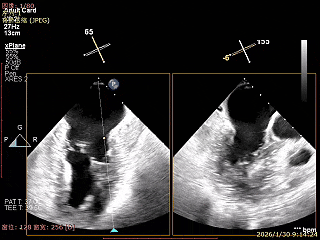

Bicomm切面看2区脱垂

X-Plane切面切1区未见明显异常

X-Plane切面切2区可见前叶Flail

X-Plane切面切3区可见前叶脱垂

3D Enface 2区及3区前叶脱向左房

3D Enface下组织桥稳定无反流

夹子释放后,反流基本消失

LVOT切面可见主瓣二尖瓣术后反流基本消失

植入两枚夹子后二尖瓣平均跨瓣压差2mmHg